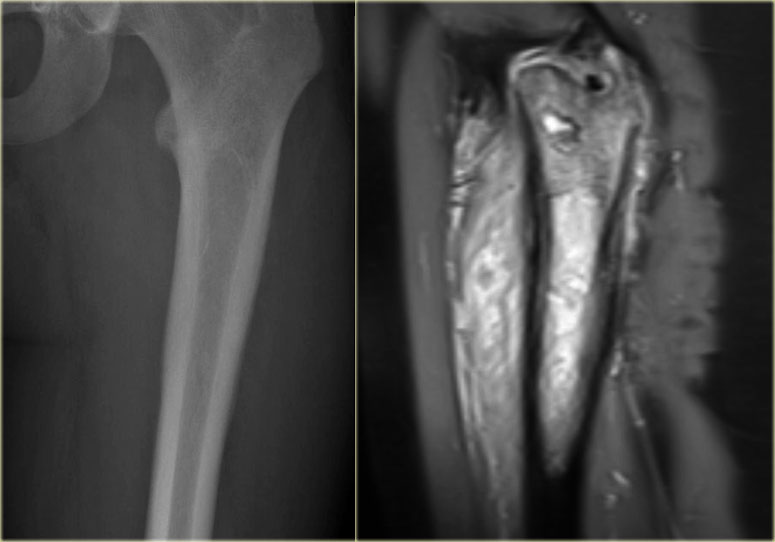

ABC

key facts:

• Aneurysmal bone cyst typically presents as a painful expansile or 'aneurysmal' well-defined osteolytic lesion in a patient younger than 30 years.

• On plain radiographs often ballooning with very thin peripheral bone shell and frequently internal thin bony ridges.

• Central or eccentric origin in the metaphysis or diaphysis of a long bone.

• In the spine located in the body or in both body and arch.

• Characteristic appearance on MR with fluid-fluid levels due to blood sedimentation.

• Peripheral enhancement of multiple small chambers is typical.

• ABC most frequently presents around the knee.

Other locations include the proximal humerus or spine, but many other bones are possible.